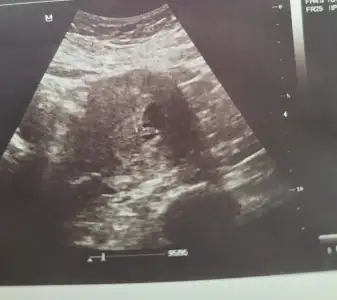

Duydum canım ayyyy nasıl rahatladım anlatamam. Hadi ilk bebis fotoğrafı benden gelsin bir de bu testleri istedi 3 gün sonraya randevu aldımHadi gözün aydın cnm çok sevindim ne testi istedi ki? Darısı başımıza inşallah kalp atımını da duydun dimi

Önemli olan bebek canım. Maşallah annesi.Kızlar bir sorum var, keseye göre bana 6 haftalık demişlerdi, bu cumartesi gittim doktora. Buna göre 7 haftalık olmam lazımdı. Sonra kalbi dinledik her şey güzeldi. Doktor bebek 6 haftalık dedi. Hocam nasıl olur, geçen hafta da 6 haftalıktı dedim. Kese ile bebeğin haftası aynı değil dedi. Sizin SAT a göre bebek ufak mı ? 1 hafta geriden geliyormuş bebek doğru mudur ?